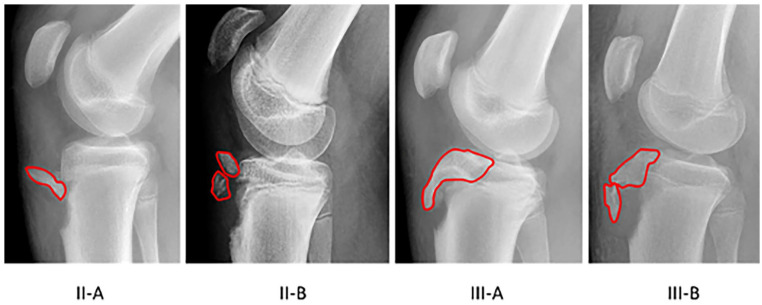

Abstract Image